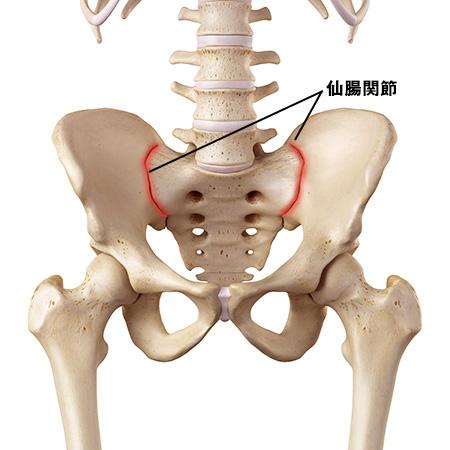

病院でレントゲン撮影しても特に異常はなく、でも数日たってもお尻の方に痛みがのこり、こちらで相談したところ、仙腸関節のズレの疑いがあるといわれ、